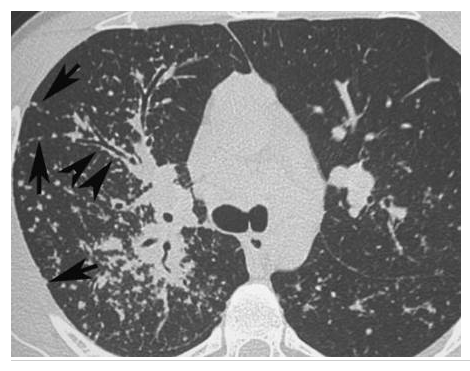

Lésions élémentaires ?

Dg ?

Sarcoïdose.

Présence de micronodules dans la région moyenne des poumons, situés en région sous-pleurale, le long des septa interlobulaires (flèches) et le long des bronches (têtes de flèches).